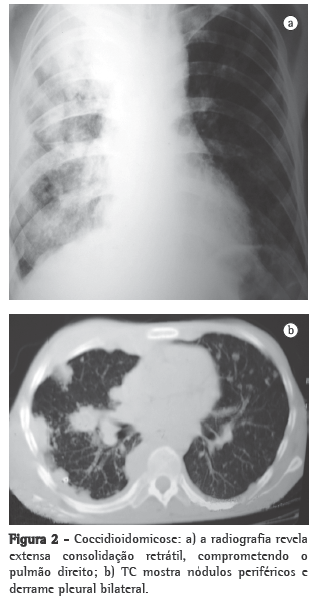

Os exames inespecíficos que são úteis para a avaliação do paciente incluem exames radiológicos e tomográficos, feitos nos sítios acometidos, principalmente no tórax, e podem auxiliar muito no diagnóstico (Figuras 2 e 3). As imagens mais frequentes ao radiograma torácico são nódulos pulmonares múltiplos de distribuição periférica, associados a consolidação parenquimatosa. Ao estudo tomográfico, os nódulos pulmonares periféricos mostram-se predominantemente escavados.(29,39)